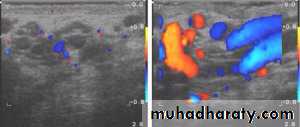

VARICOCELE

It is a varicose dilatation of the veins draining the testis ( abnormal dilatation of the pampiniform plexus)Most varicoceles present in adolescence or early adulthood

Usually on the left.

On palpation, with the patient standing, the varicose plexus feels like a bag of worms.

Investigations: Scrotal Doppler U/S